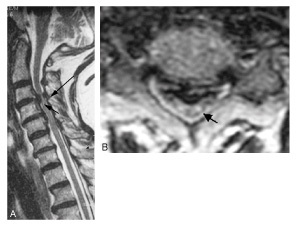

Quel diagnostic?

myélopathie cervicarthrosique C4-C5 avec hypersignal médullaire